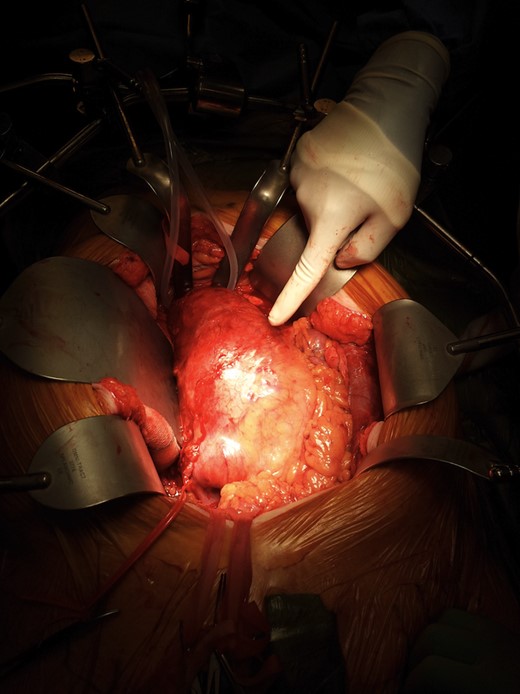

A diagnosis of large AAA causing PE was made as it was found to be displacing and compressing the IVC, and causing venous thromboembolism. During the open repair of aortoiliac aneurysm, findings of venogram were confirmed, as aneurysm was found to be compressing IVC (Fig. 6). A large plaque was removed from the aneurysmal sac. A bifurcation synthetic graft was placed for inlay reconstruction, and the abdomen was closed in layers. Her recovery period was uneventful. She was able to sit on the chair on Day 3 after surgery and was mobilizing well in a week time.